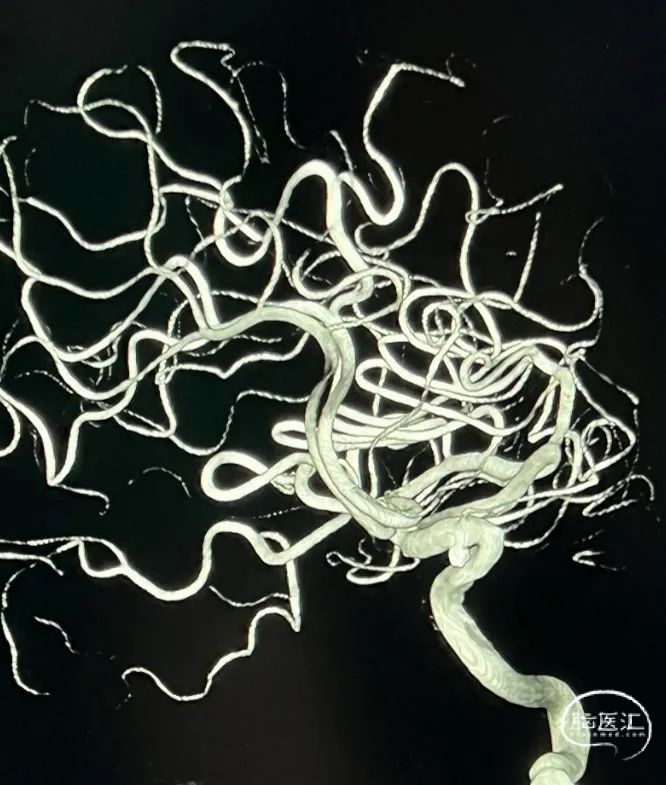

DSA:L-C5 AN,大小约2.5mm*2.3mm。

术前3D:动脉瘤大小约2.52*2.34mm,颈宽约2.38mm,载瘤动脉近端约3.63mm,远端4.08mm。

支架:Neuroform Atlas 4.5*21mm

左侧颈内动脉迂曲,在SL-10微导管及Synchro微导丝配合下将6F Envoy输送至左侧岩骨段近端。

预填部分2mm*4cm Target弹簧圈进行成篮,然后将4.5*21mm Atlas支架到位并进行半释放,半释放支架后,继续填入2mm*4cm Target弹簧圈。

将Atlas支架全部释放(如左动态影像)

Target 2mm*4cm弹簧圈成篮满意,支架打开良好。

该病例中,弹簧圈均匀致密填充动脉瘤瘤体,得益于Target弹簧圈独特的360结构设计,具备顺应成篮和向心性填充的特性,并且填塞过程中几乎无踢管。

Atlas顺应性和贴壁性能均优于其他品牌支架,并且具有足够的径向支撑力,与Target联合使用,效果满意。